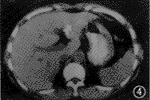

1.临床疗效判定: 栓塞前CT平扫见有低密度区域,增强见典型“早出晚归”现象。DSA显示早动脉期即出现边界锐利的点状血窦,沿瘤体周边分布,随时间推移,瘤体染色自外周向中心扩展,边界变得模糊,血窦染色排空明显延迟。注入PLE后6例CHL肿瘤血窦均明显染色(图1,2)。栓塞后1~6个月CT平扫见瘤体内碘油沉积,肿瘤直径明显缩小(图3,4)。栓塞前肿瘤直径平均为(6.8±1.5) cm,栓塞后平均为(2.5±2.1) cm。栓塞前后肿瘤直径经t检验,有显著性差异(t=4.485,P<0.05)(表1)。

图4 栓塞后CT平扫见肝左叶团状碘油沉积,长径为2.5 cm